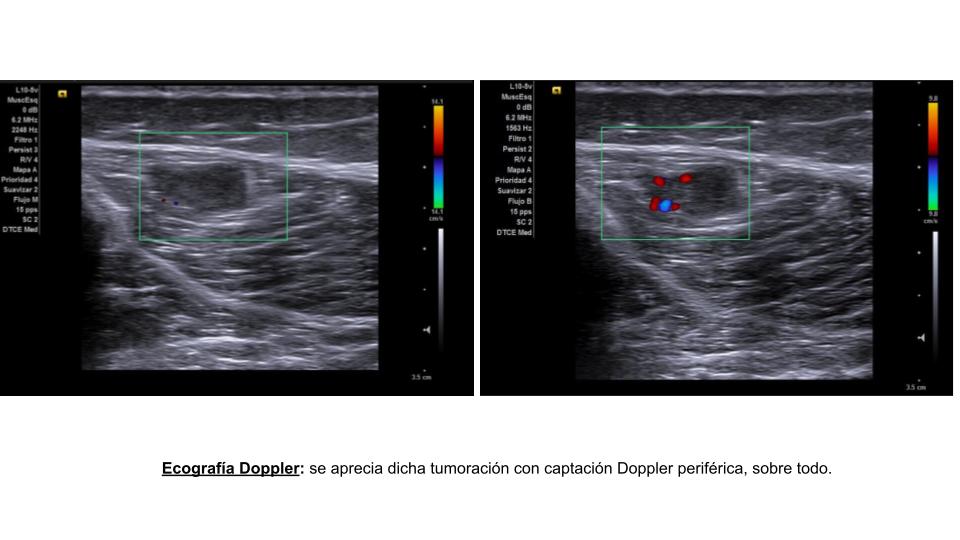

En ecografía clínica se aprecia en tercio medio de la pierna, en gemelo externo, una lesión hipoecoica, polilobulada y heterogénea, de márgenes definidos, con flujo Doppler central y periférico, de 1,7 x 5,8 x 11,6 mm.